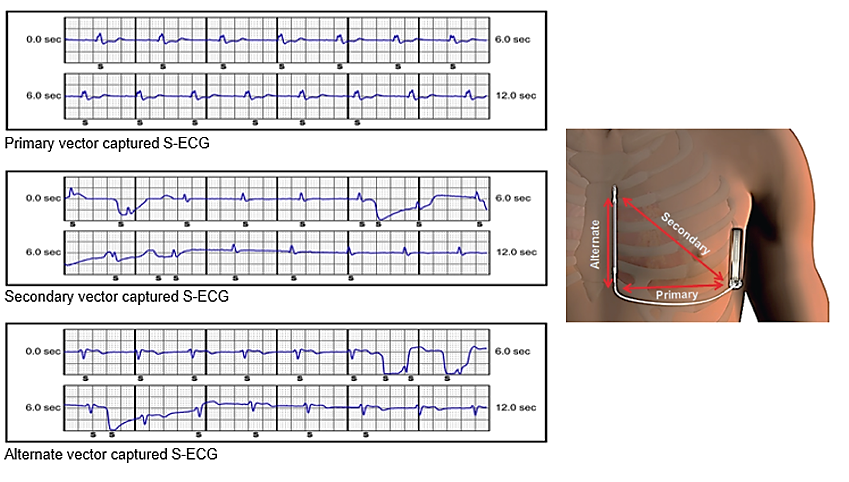

The following day a post implant check was performed. The check revealed multiple stored ‘untreated’ arrhythmia episodes. An example of an episode is displayed in figure 1. The check also revealed some baseline wander in the secondary and alternate sensing vectors, but not in the primary vector (figure 2). Device settings are displayed below.

Figure 1 – Example 1 showing a subcutaneous ECG (S-ECG) untreated episode recording discovered at the post implant check. The sensing vector programmed is the secondary configuration.